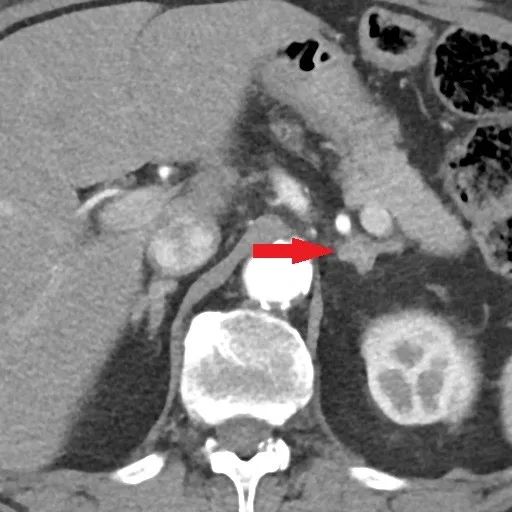

术前肾上腺增强CT检查:左侧肾上腺腺瘤。

图1. 红色箭头指向左侧肾上腺腺瘤。